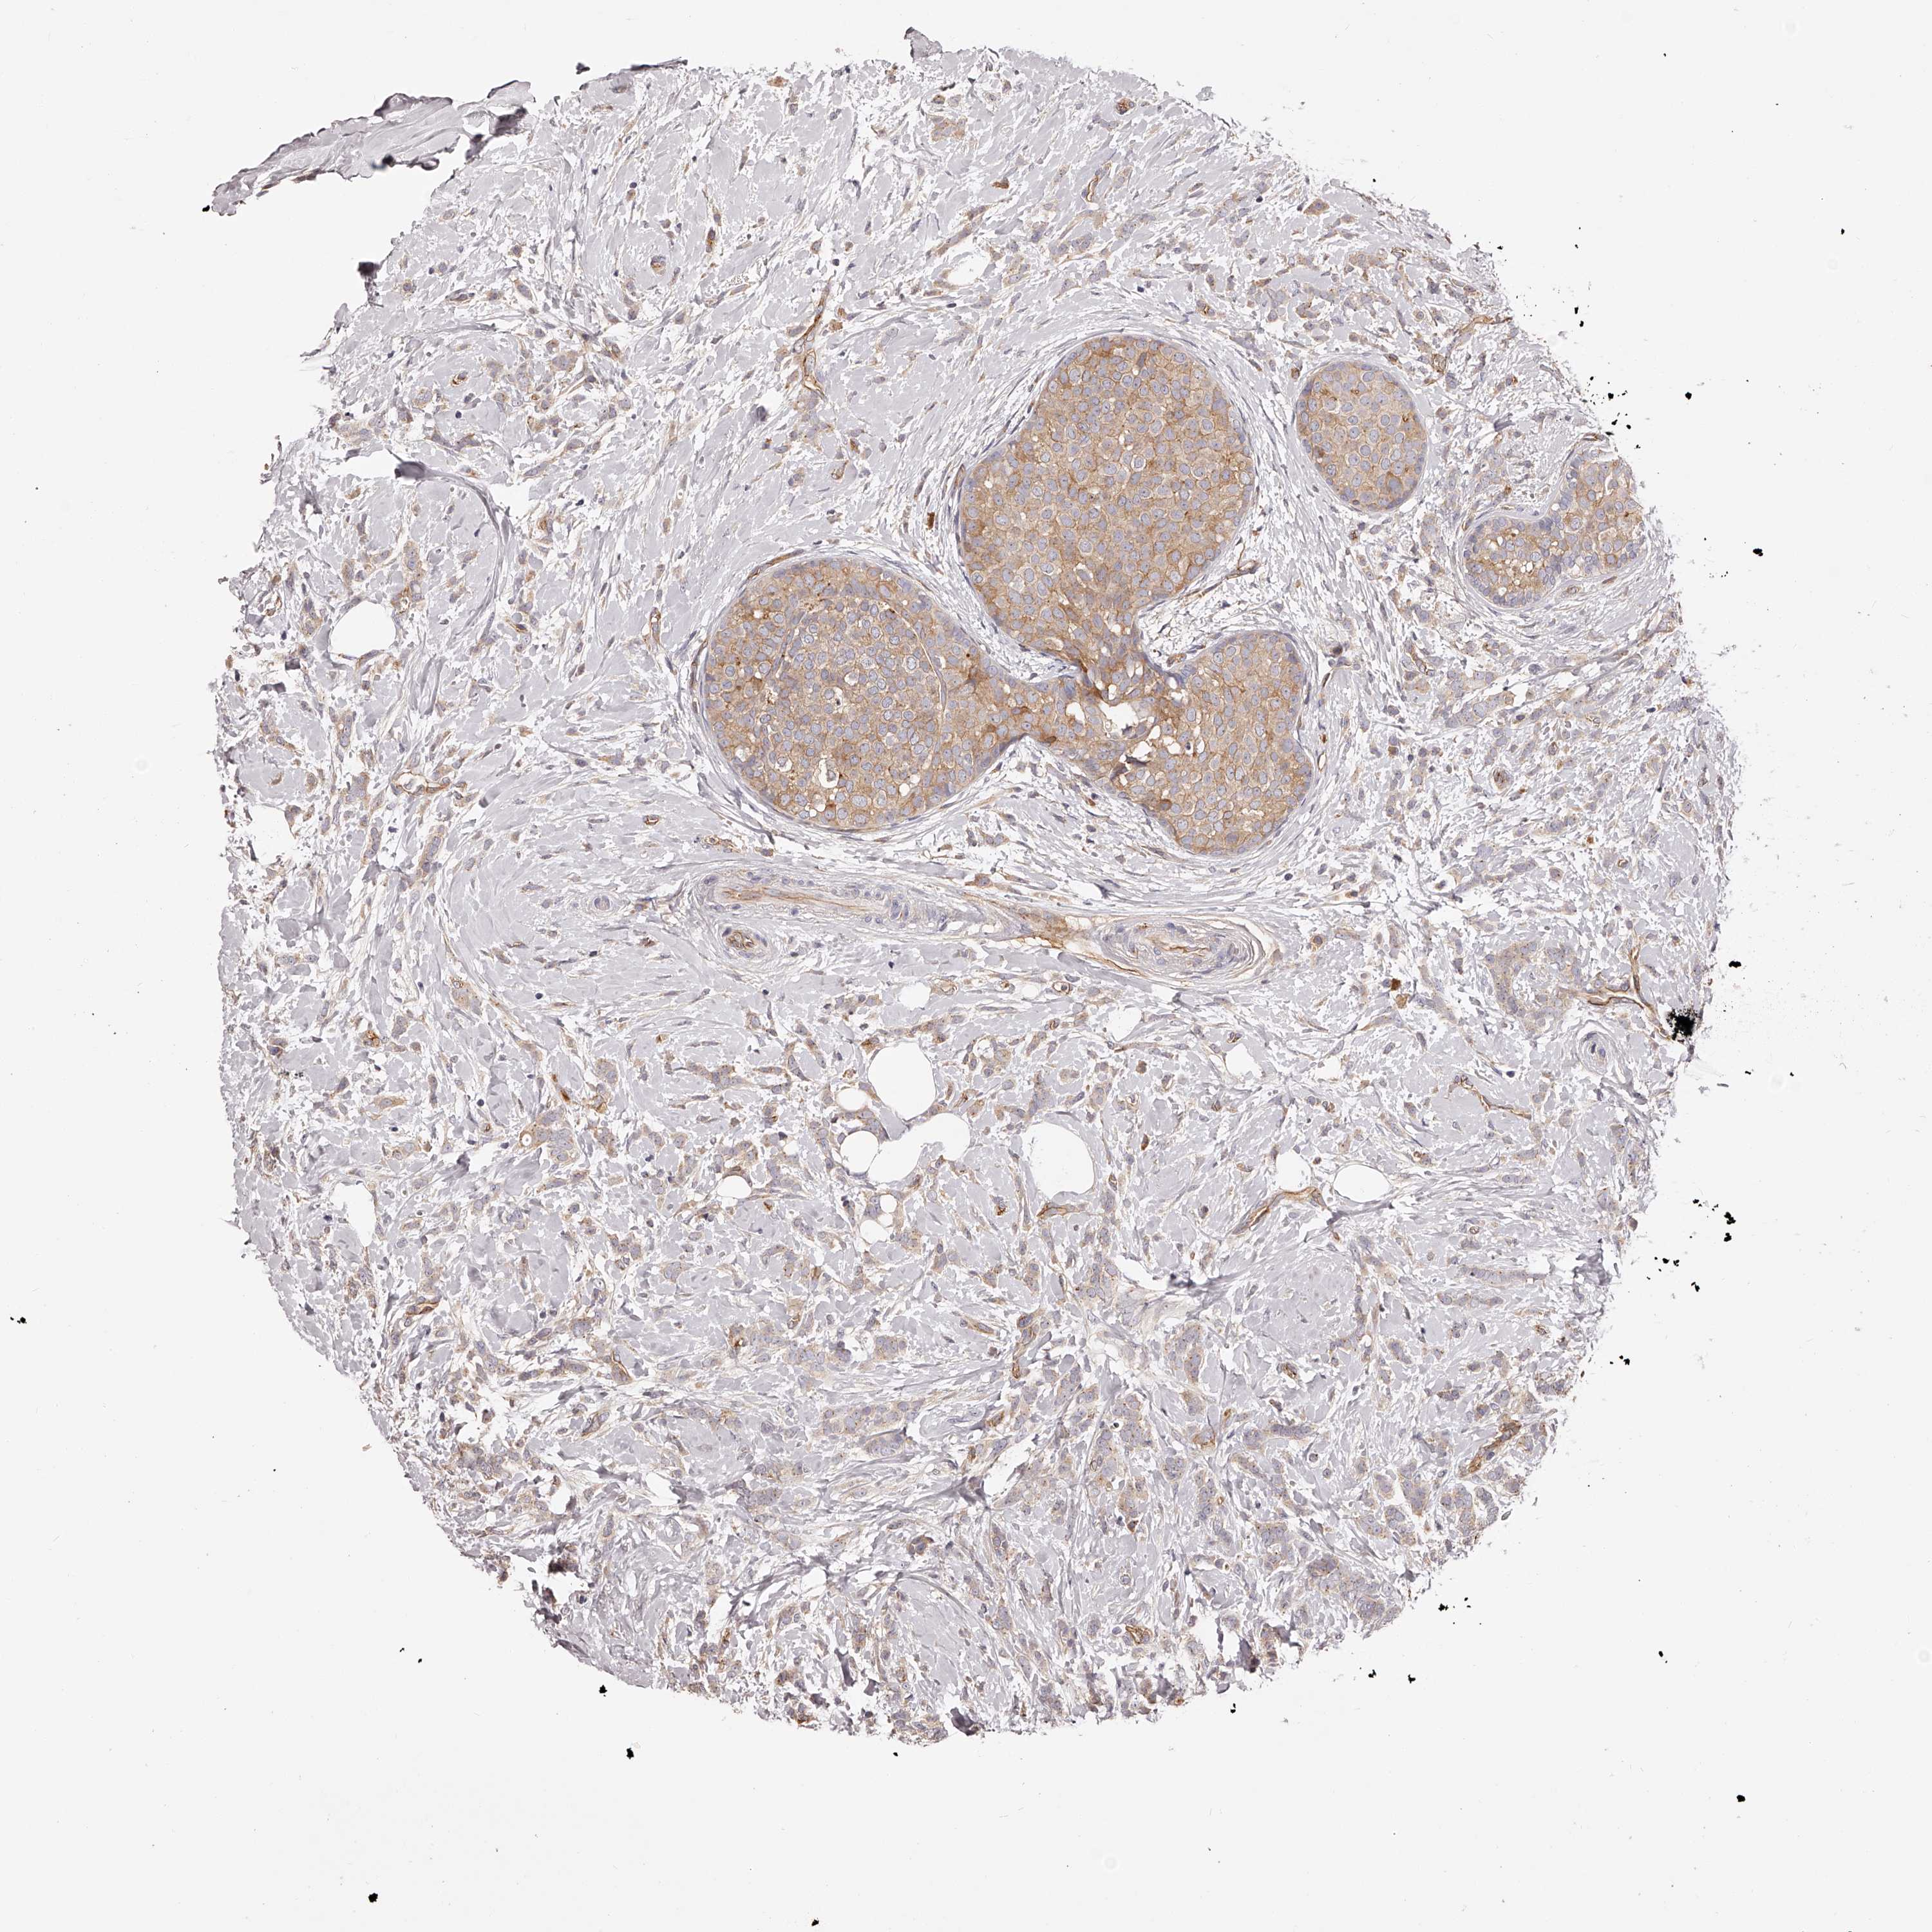

CANCER BREAST CANCER Show tissue menu

BRCA TCGA BRCA VALIDATION PROTEIN EXPRESSION